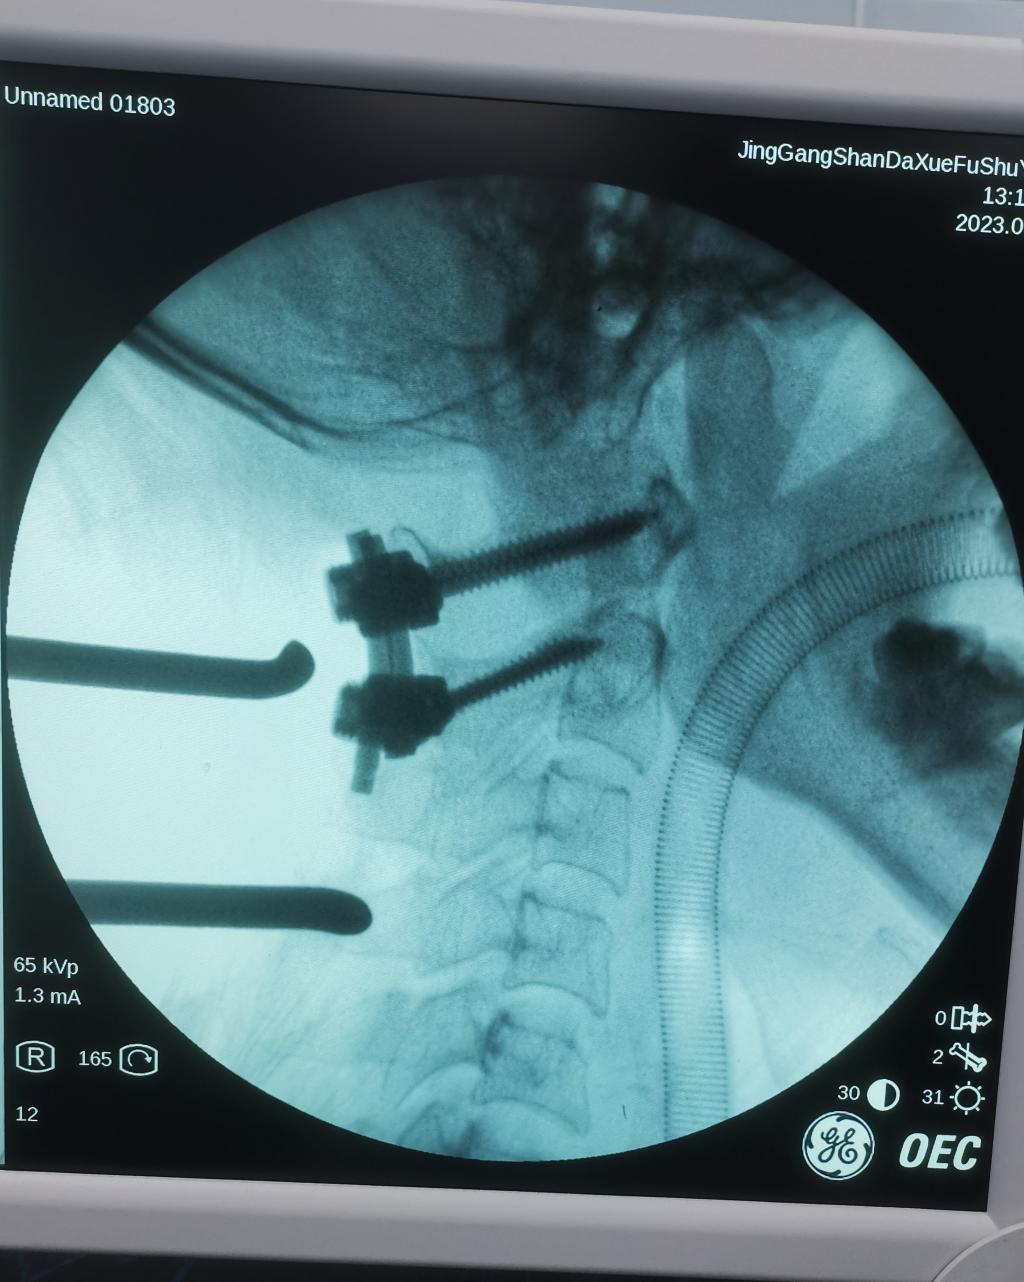

以往此类骨折,患者均需转院省城医院。入院后,肖强教授带领我院骨科脊柱团队详细检查病人及审阅患者影像资料,认为患者齿状突骨折Ⅱ型,寰枢椎不稳,手术指征明确,为方便患者的就医,肖强教授决定利用国庆假期,在我院为患者行手术治疗。经过充分术前准备,制定了周密手术计划,于9月30日成功完成了颈后路寰枢椎椎弓根螺钉内固定术,术中透视,齿突骨折解剖复位,寰枢椎椎弓根螺钉位置良好,手术顺利,出血约50毫升,历时约1小时,术后患者状态恢复良好,现佩戴颈托已下地活动。

术中完美置钉